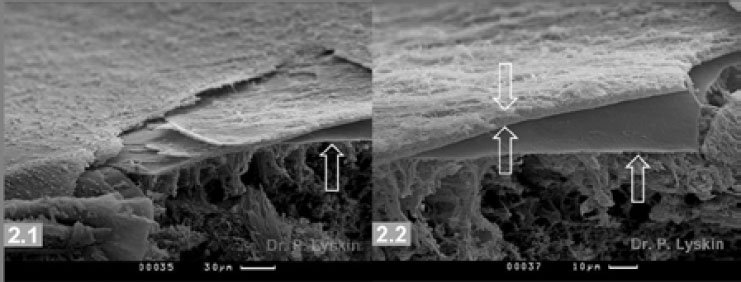

При исследовании парамакулярных отделов выявлено, что на поверхности сетчатки остался тонкий слой СТ, расположенный на поверхности ВПМ (рис. 1.2–1.4). Монослой состоял из тонких, плотно упакованных волокон СТ (см. рис. 1.4). Толщина обнаруженного слоя составила около 5 мкм (рис. 1.4, 2.2). Обнаруженный тонкий слой СТ был плотно соединён с ВПМ по всей поверхности и имел мембраноподобную моноструктуру (см. рис. 1.3). Обнаруженный эпиретинальный слой СТ в свою очередь обладал слоистой структурой (рис. 2.1).

Рис. 2. Поверхность сетчатки после удаления основного стекловидного тела (СТ). 2.1. Эпиретинальное СТ. Внутренняя пограничная мембрана (ВПМ) указана стрелкой. Эпиретинальное СТ имеет слоистую структуру. 2.2. ВПМ указана стрелкой снизу. Эпиретинальный слой СТ указан двумя оппозитными стрелками. Толщина эпиретинального СТ 3–5 мкм. Волокна в слое плотно упакованы

Выявлены очевидные различия в толщине и плотности упаковки волокон СТ в 5-микронном слое эпиретинального СТ. Со стороны ВПМ у её поверхности волокна эпиретинального СТ имеют наименьший диаметр и наиболее плотно упакованы (см. рис. 1.4, 2.2). На поверхности эпиретинального СТ, граничащей с основным СТ, коллагеновые волокна имеют наибольший диаметр, длину и наименьшую плотность упаковки (см. рис. 3.2–3.4).

Результаты проведённых исследований показали, что после удаления основного СТ и его кортикальных слоёв, произведённого в процессе подготовки препарата, на поверхности сетчатки остаётся тонкий слой эпиретинального СТ. Толщина парамакулярного эпиретинального СТ составляет 3–5 мкм. Эпиретинальный слой СТ образован в основном тонкими, плотно упакованными волокнами СТ.